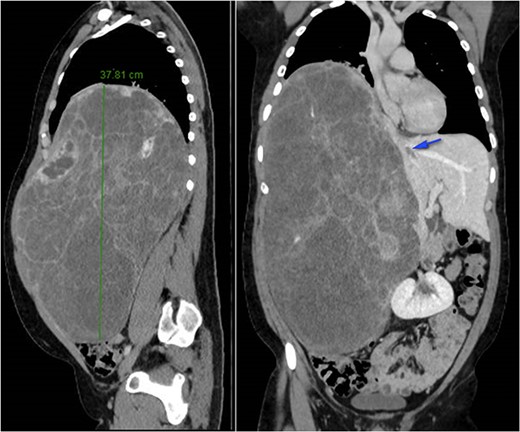

A 26-year-old, previously healthy man was admitted in March 2019 to the Surgical Department of our Hospital with abdominal distension and discomfort in the last 6 months. On physical examination, a palpable large mass was documented in the right hypochondrium extending below the umbilicus with tenderness in the upper abdomen without evidence of ascites. His medical history was little significant, just fraternal twin and hypothyroidism. Laboratory tests were carried out but tumour markers, hepatitis virus markers, and liver enzymes were normal and not diagnostic. Contrast enhanced CT-scan highlighted a giant, hypodense, heterogeneous, solid lesion without cystic component in the right lobe of the liver (Fig. 1). The tumour compressed neighbouring parenchyma and displaced abdominal organs and the retro-hepatic vena cava was also compressed with the middle hepatic vein slightly occluded by thrombotic material. Percutaneous needle biopsies were performed in different areas of the mass. All samples showed mesenchymal tissue with low proliferative index MIB1, and the pathologist suggested diagnosis of MHL. Following a thorough review of the literature, in view of the possibility of malignant degeneration and the high rate of local recurrence, radical liver surgery was proposed. Liver volumetry was measured, and the future liver remnant appeared sufficient to avoid post-operative liver failure. For this reason, liver transplantation was ruled out in favour of right hemi-hepatectomy without segment 1, according to Brisbane classification. In April 2019, the patient was admitted in operatory room after resolution of the middle hepatic vein thrombus with anticoagulant therapy. Right hepatectomy was carried out in 330 min.

At 42 months follow-up liver function tests were normal and CT-scan performed 6 months, 1–2–3 years after surgery were negative for disease recurrence (Fig. 2).